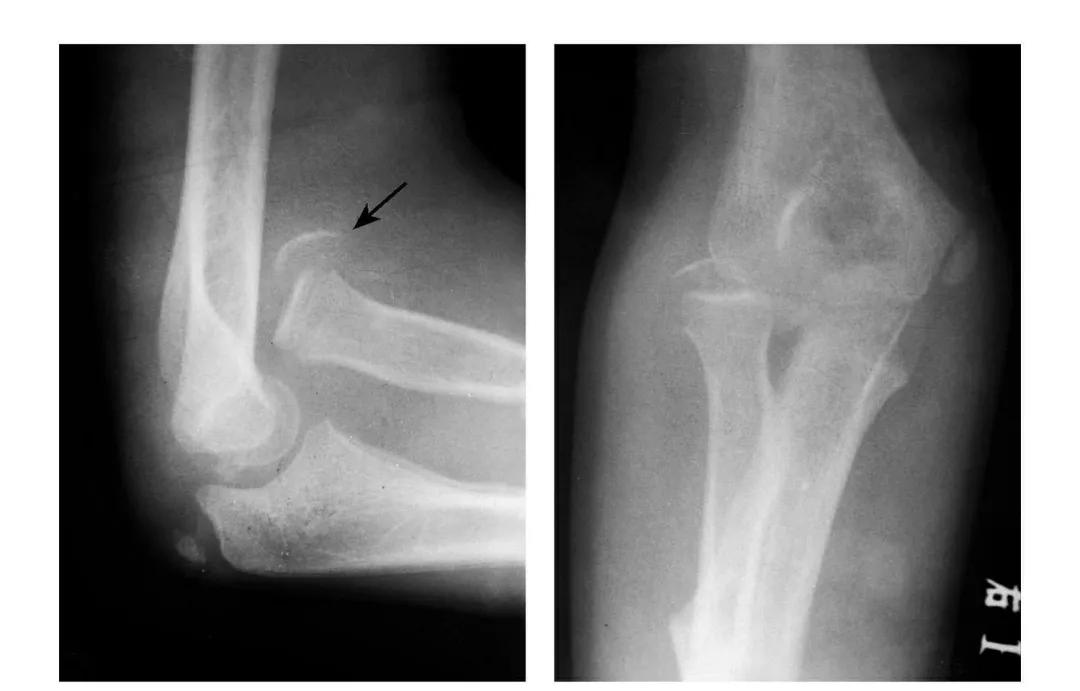

尺骨冠状突骨折

例1:尺骨冠状突撕脱骨折,骨块移向肘前上方。

例2:尺骨冠状突基底骨折,致肘关节不稳,当伸肘位时,肘关节易呈后脱位状。

例3:尺骨冠状突基底部劈裂性骨折,骨块向前外移位并上尺桡关节分离。